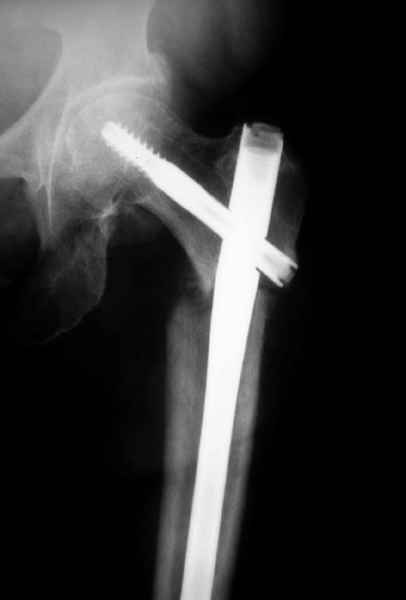

77 летняя больная направлена в нашу клинику на дальнейшее лечение. Из истории, травму получила в сентябре 2007 года и по поводу перелома шейки бедра больная была проперирована тремя каннюлированными шурупами с явным нарушением технологии установки шурупов. Внизу вместо одного шурупа имеется два, что привело к стрессу латерального кортекса. Через месяц по поводу ятрогенного подвертельного перелома сделана фиксация длинной Гамма 3. Установлен без проксимальной блокировки? (set screw). В данный момент имеется несостоятельность конструкции и ложный сустав. Передвигается с помошью костылей, конечность укорочена на 2 см. Какие будут рекомендации?Djoldas Kuldjanov, MDDepartment of Orthopedic SurgerySt. Louis University Medical Center

Видимо, проблем тут две: во-1-х, центральный отломок был оставлен в варусно-сгибательной установке, во-2-х, не динамизировали вовремя.

Нижние винты хотели сломаться, но, увы, один не сломался, и тогда сломался гвоздь. Хотя и при динамизации в таком положении отломков

могло не срастись.

Не стали усложнять интрамедуллярным вариантом коррекции, легче контролировать коррекцию пластиной, поэтому сделали операцию 95 градусной Blade Plate, разогнув до 110 градусов.

Надеемся на успех, потому что до введения пластины дефект от импланта забили костной стружкой и удалось создать компрессию между отломками, максимальную для импланта (150 кило/паунд). Сделана дополнительная костная пластика и за счет измененного угла пластины устранено укорочение конечности.